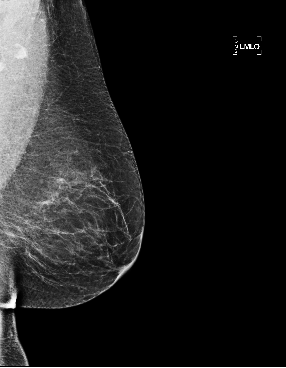

Based on these results, we submitted our final architecture described in Section 2 for testing on the large GH-Validation dataset. In the first sub-challenge, which records the AUC by breast purely on imaging and blinded to demographic information, we achieved AUC=0.879 (standard deviation: 0.00914), see Fig. 2(e), which is 0.005 above the top AUC in the competitive phase of the Challenge. It was also the highest single-model AUC in the collaborative phase, 0.014 below an ensemble of detection models, and higher than all patch-based models. The second sub-challenge is on subject-wise AUC, with access to both images and demographics. Despite ignoring demographics, our architecture gave AUC=0.868, behind only the top score in the competitive phase (a patch-based curriculum-trained model) by 0.006. Twenty-five method descriptions from this phase are available at synapse.org, but details of the collaborative phase, including performance of patch-based models trained on Optimam, is embargoed pending publication by the Challenge. Fig. 2 shows sample outputs from GH.

Refer to caption

Figure 2: (a) True positive prediction (p=0.90𝑝0.90p=0.90 probability of malignancy) of an inconspicuous lesion on a left MLO of a 73 year old woman. (b) True negative (malignancy: p=0.06𝑝0.06p=0.06) for left MLO view of a 66 year old woman. (c) False positive (p=0.78𝑝0.78p=0.78) on left MLO of a 43 year old woman, due to hyper-intense region. (d) False negative (p=0.03𝑝0.03p=0.03) for left CC view of a 61 year old woman. (e) ROC by breast, AUC = 0.879.